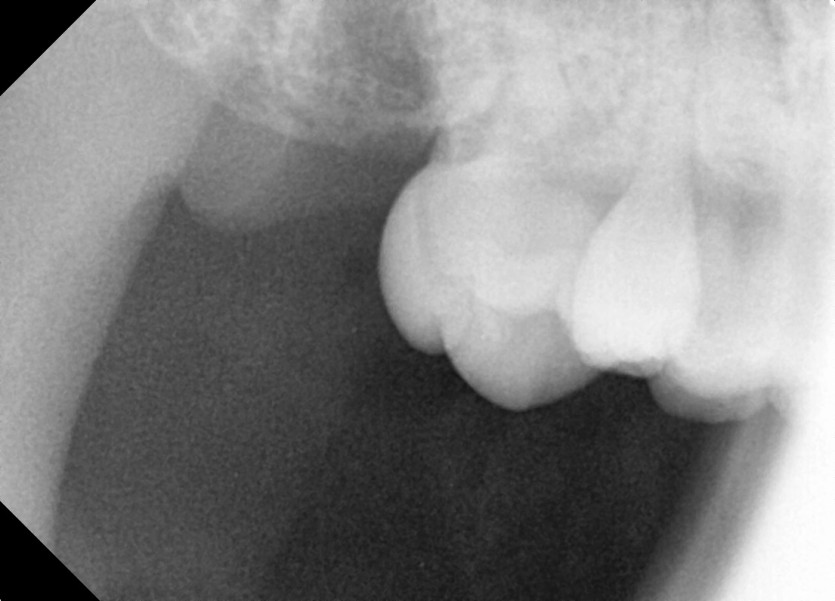

#18,28,38,48 사랑니 발치

구강 외과 전문의가 당일 발치했습니다.